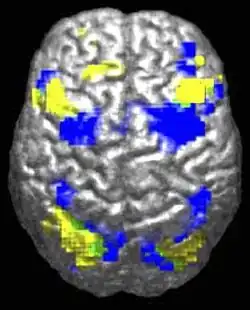

Structure cérébrale

Des différences au niveau du cerveau ont été observées chez les personnes autistes, apportant une signature anatomique à la définition antérieure par des critères cliniques. Les études en neurosciences ont montré des différences dans l’organisation du cortex[38],[39], au niveau des dendrites (arborescences des neurones) et des synapses (connexion entre neurones), voire des modifications plus larges de structures cérébrales. Il est possible que les différences corticales apparaissent au cours d'un stade de développement anténatal[38].

En corrélation avec les différences fonctionnelles observées au niveau comportemental, les études d'Eric Courchesne et de son équipe relèvent que les enfants autistes ont un nombre de neurones plus élevé de 67 % en moyenne dans le cortex préfrontal[40], et une croissance cérébrale plus importante que la moyenne au niveau des lobes frontaux, ce qui s'est traduit dans la littérature scientifique antérieure par des observations de périmètre crânien plus élevé[41].